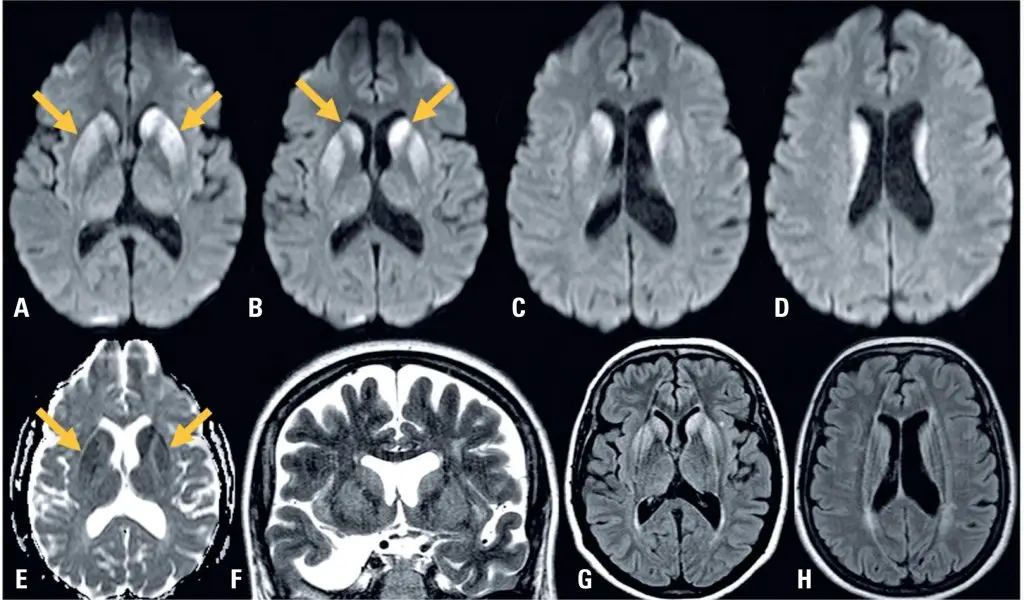

A 53-years old white women was presented with a four-weeks history of unsteady gait, followed by mental confusion and progressive memory loss. Neurological examination revealed axial ataxia, short-term memory loss, and brisk deep tendon reflexes in all limbs. Brain MRI () revealed a diffusion signal abnormality involving the bilateral caudate heads and putamen, with no cortical changes. Cerebrospinal fuid (CSF) analysis showed 1 cells per μL, protein content of 25.5 mg/dL, and glucose content of 58 mg/dL. Eletroencefalograma revealed no periodic sharp wave complexes. Real-time quaking-induced conversion (RT-QuIC) test and 14-3-3 protein detection in the CSF were both positive. Eight-weeks later, multifocal myoclonus developed, and death occurred shortly thereafter.

Sporadic Creutzfeldt-Jakob disease (CDJ) is a fatal, rapidly progressive neurodegenerative disease that was first described as a dementia syndrome associated with cortical, striatal, and spinal cord involvement.() Its pathogenesis is related to the alteration of a naturally existing prion protein (PrPc) to an abnormal folder protein termed scrapie prion protein (PrPSc), and its clinical presentation can vary.() Brain MRI findings, especially those derived from diffusion-weighted imaging, play a pivotal role in recognizing and distinguishing sCJD from alternative diagnoses. Abnormal cortical signal intensity on MRI exhibits sensitivity, specificity, and accuracy exceeding 90% for sCJD.() However, abnormalities in the deep gray matter represent atypical MRI findings are even rarer.() Our case was characterized by significant basal ganglia imaging and less cortical involvement, which may pose challenges in cases with similar presentations.